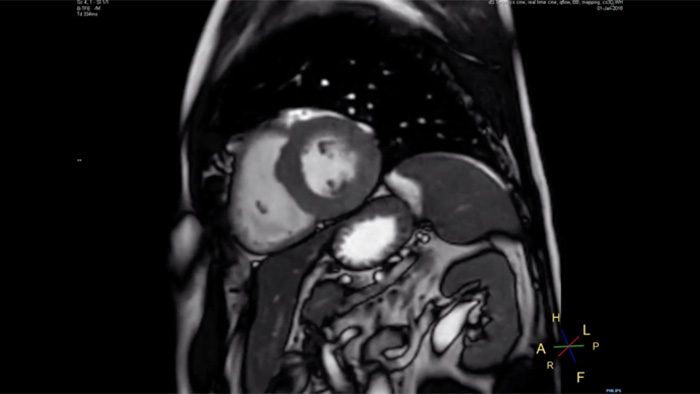

Philips Compressed SENSE riduce il tempo trascorso dal soggetto all'interno dallo scanner di RM. Consente inoltre di abbreviare i tempi di apnea agevolando la fattiva collaborazione del paziente.

Tempo di apnea di 4,8 secondi

Poiché i tempi di apnea brevi facilitano la fattiva collaborazione dei pazienti, l'impossibilità per loro di trattenere il respiro è un problema che si presenta ormai raramente.

Nella nostra struttura, abbiamo riscontrato che nella RM cardiaca sono necessarie meno apnee o che i tempi di apnea si sono ridotti."

Dott. Takashi Koyama, radiologo diagnostico e direttore del reparto di radiologia del Kurashiki Central Hospital (Giappone)

Per molti pazienti cardiaci, trattenere il respiro per 15 o 16 secondi è un compito arduo. Grazie a Compressed SENSE, disponiamo ora di protocolli che riducono l'apnea al di sotto dei 10 secondi. Così per loro è molto più facile e, quindi, sono anche molto più soddisfatti dell'esperienza."

Dott. Trevor Andrews, fisico della risonanza magnetica della University of Vermont Medical Center (Stati Uniti)